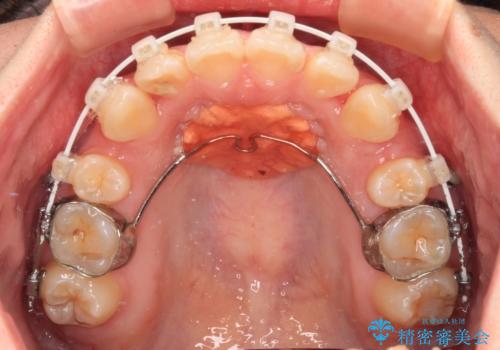

- 矯正装置

- 審美装置

- 上下前歯のデコボコを気にして来院された患者様です。

口元の突出感はあまりなかったものの、デコボコを非抜歯で改善すると出っ歯になる可能性があるため、上下左右の第一小臼歯4本を抜歯し、ワイヤー装置にて矯正治療を行うこととしました。

口元の突出感はなかったものの、捻転や八重歯を改善するために補助装置を併用する必要がありました。

予定の2年半を越えてしまいましたが、無事にきれいな口元に仕上げることができました。